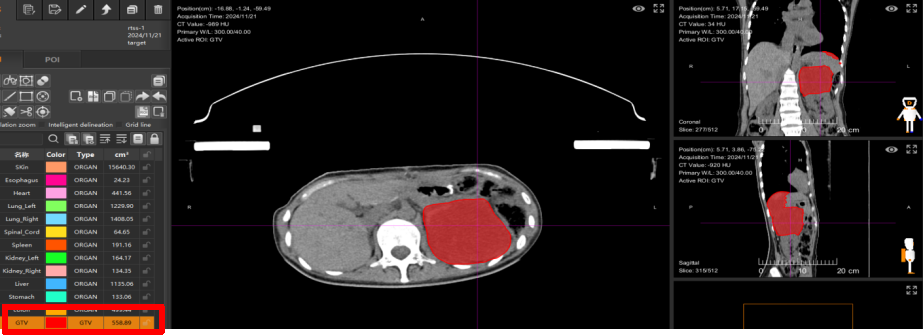

4. 重(碳)离子治疗与疗效 行重(碳)离子治疗局部根治性治疗。治疗前(2024年11月5日):CT显示腹腔内巨大肿瘤,肿瘤体积为1384.98 cm³。患者因疼痛无法弯腰,行走困难。治疗5次后(2024年11月21日):复查CT显示肿瘤明显缩小,肿瘤净体积缩小至558.89 cm³,体积缩小率为60%。临床症状改善:仅治疗2次后,患者腰背部疼痛即得到显著缓解,可正常行走。治疗结束时影像显示,与治疗前相比,肿瘤已被灭活,体积大幅缩小,并处于吸收消散过程中。

转至武威重离子中心接受重(碳)离子治疗,2024年11月5日,重(碳)离子治疗计划,治疗前肿瘤体积:1384.98cm3。红色为肉瘤部分。

在武威重离子中心接受重(碳)离子治疗,治疗前肿瘤净体积:1384.98 cm3,治疗5次肿瘤净体积缩小为:558.89cm3,肿瘤体积缩小了60%。

左图为重(碳)离子治疗前2024年11月5日,示肿瘤大小,约120mm。右图为重(碳)离子治疗结束时,见肿瘤已灭活,明显缩小,正在吸收消散中。